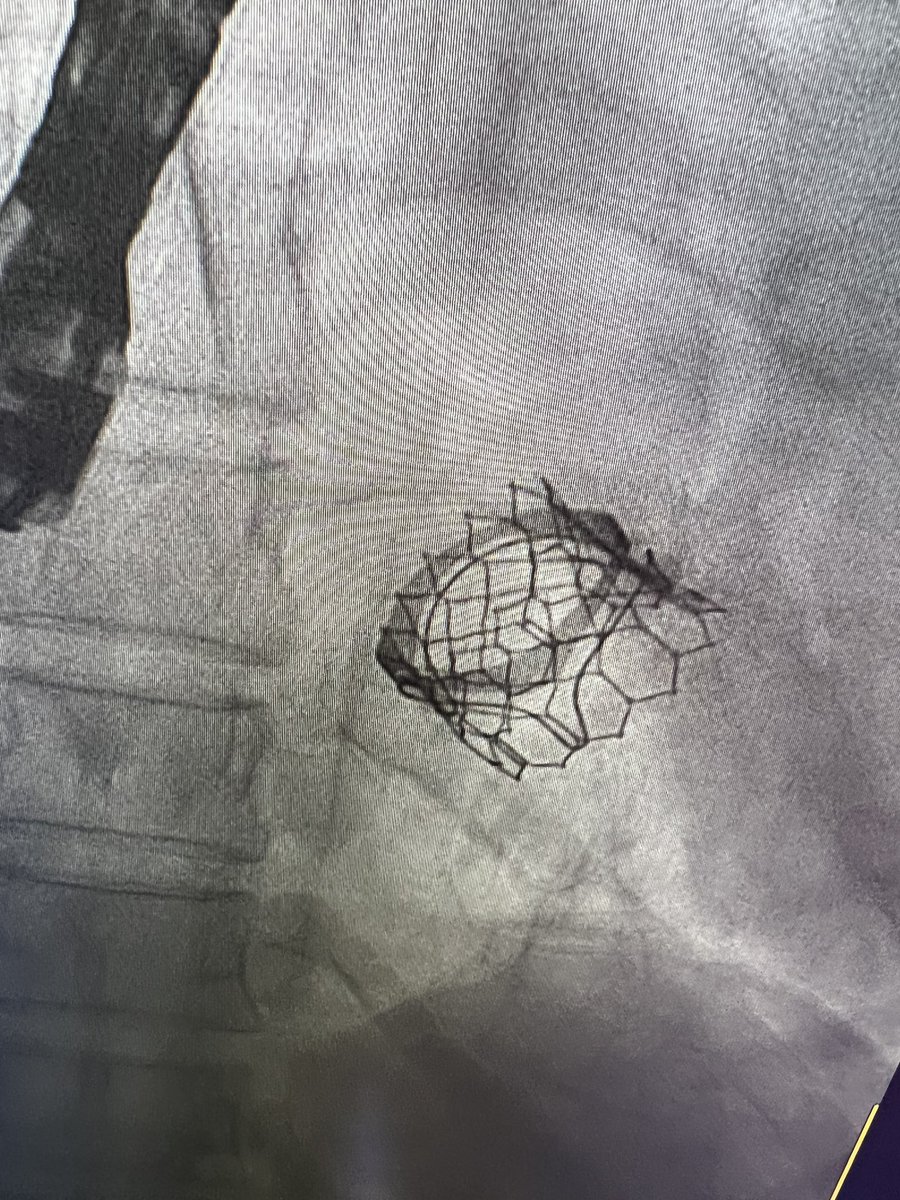

مريضتنا تعاني من كتمه شديده بالنفس ادت الى تقييد الحركه نتيجة تضيق صمام مايترال جراحي قبل عدة سنوات اصبح بالامكان الان العلاج عن طريق القسطره وتركيب صمام جديد كانت العمليه ناجحه ولله الحمد وتم خروج المريضه من المستشفى بدون اي اعراض ولله الحمد شكرا للفريق المشارك

مريضتنا تعاني من كتمه شديده بالنفس ادت الى تقييد الحركه نتيجة تضيق صمام مايترال جراحي قبل عدة سنوات

اصبح بالامكان الان العلاج عن طريق القسطره وتركيب صمام جديد

كانت العمليه ناجحه ولله الحمد وتم خروج المريضه من المستشفى بدون اي اعراض ولله الحمد